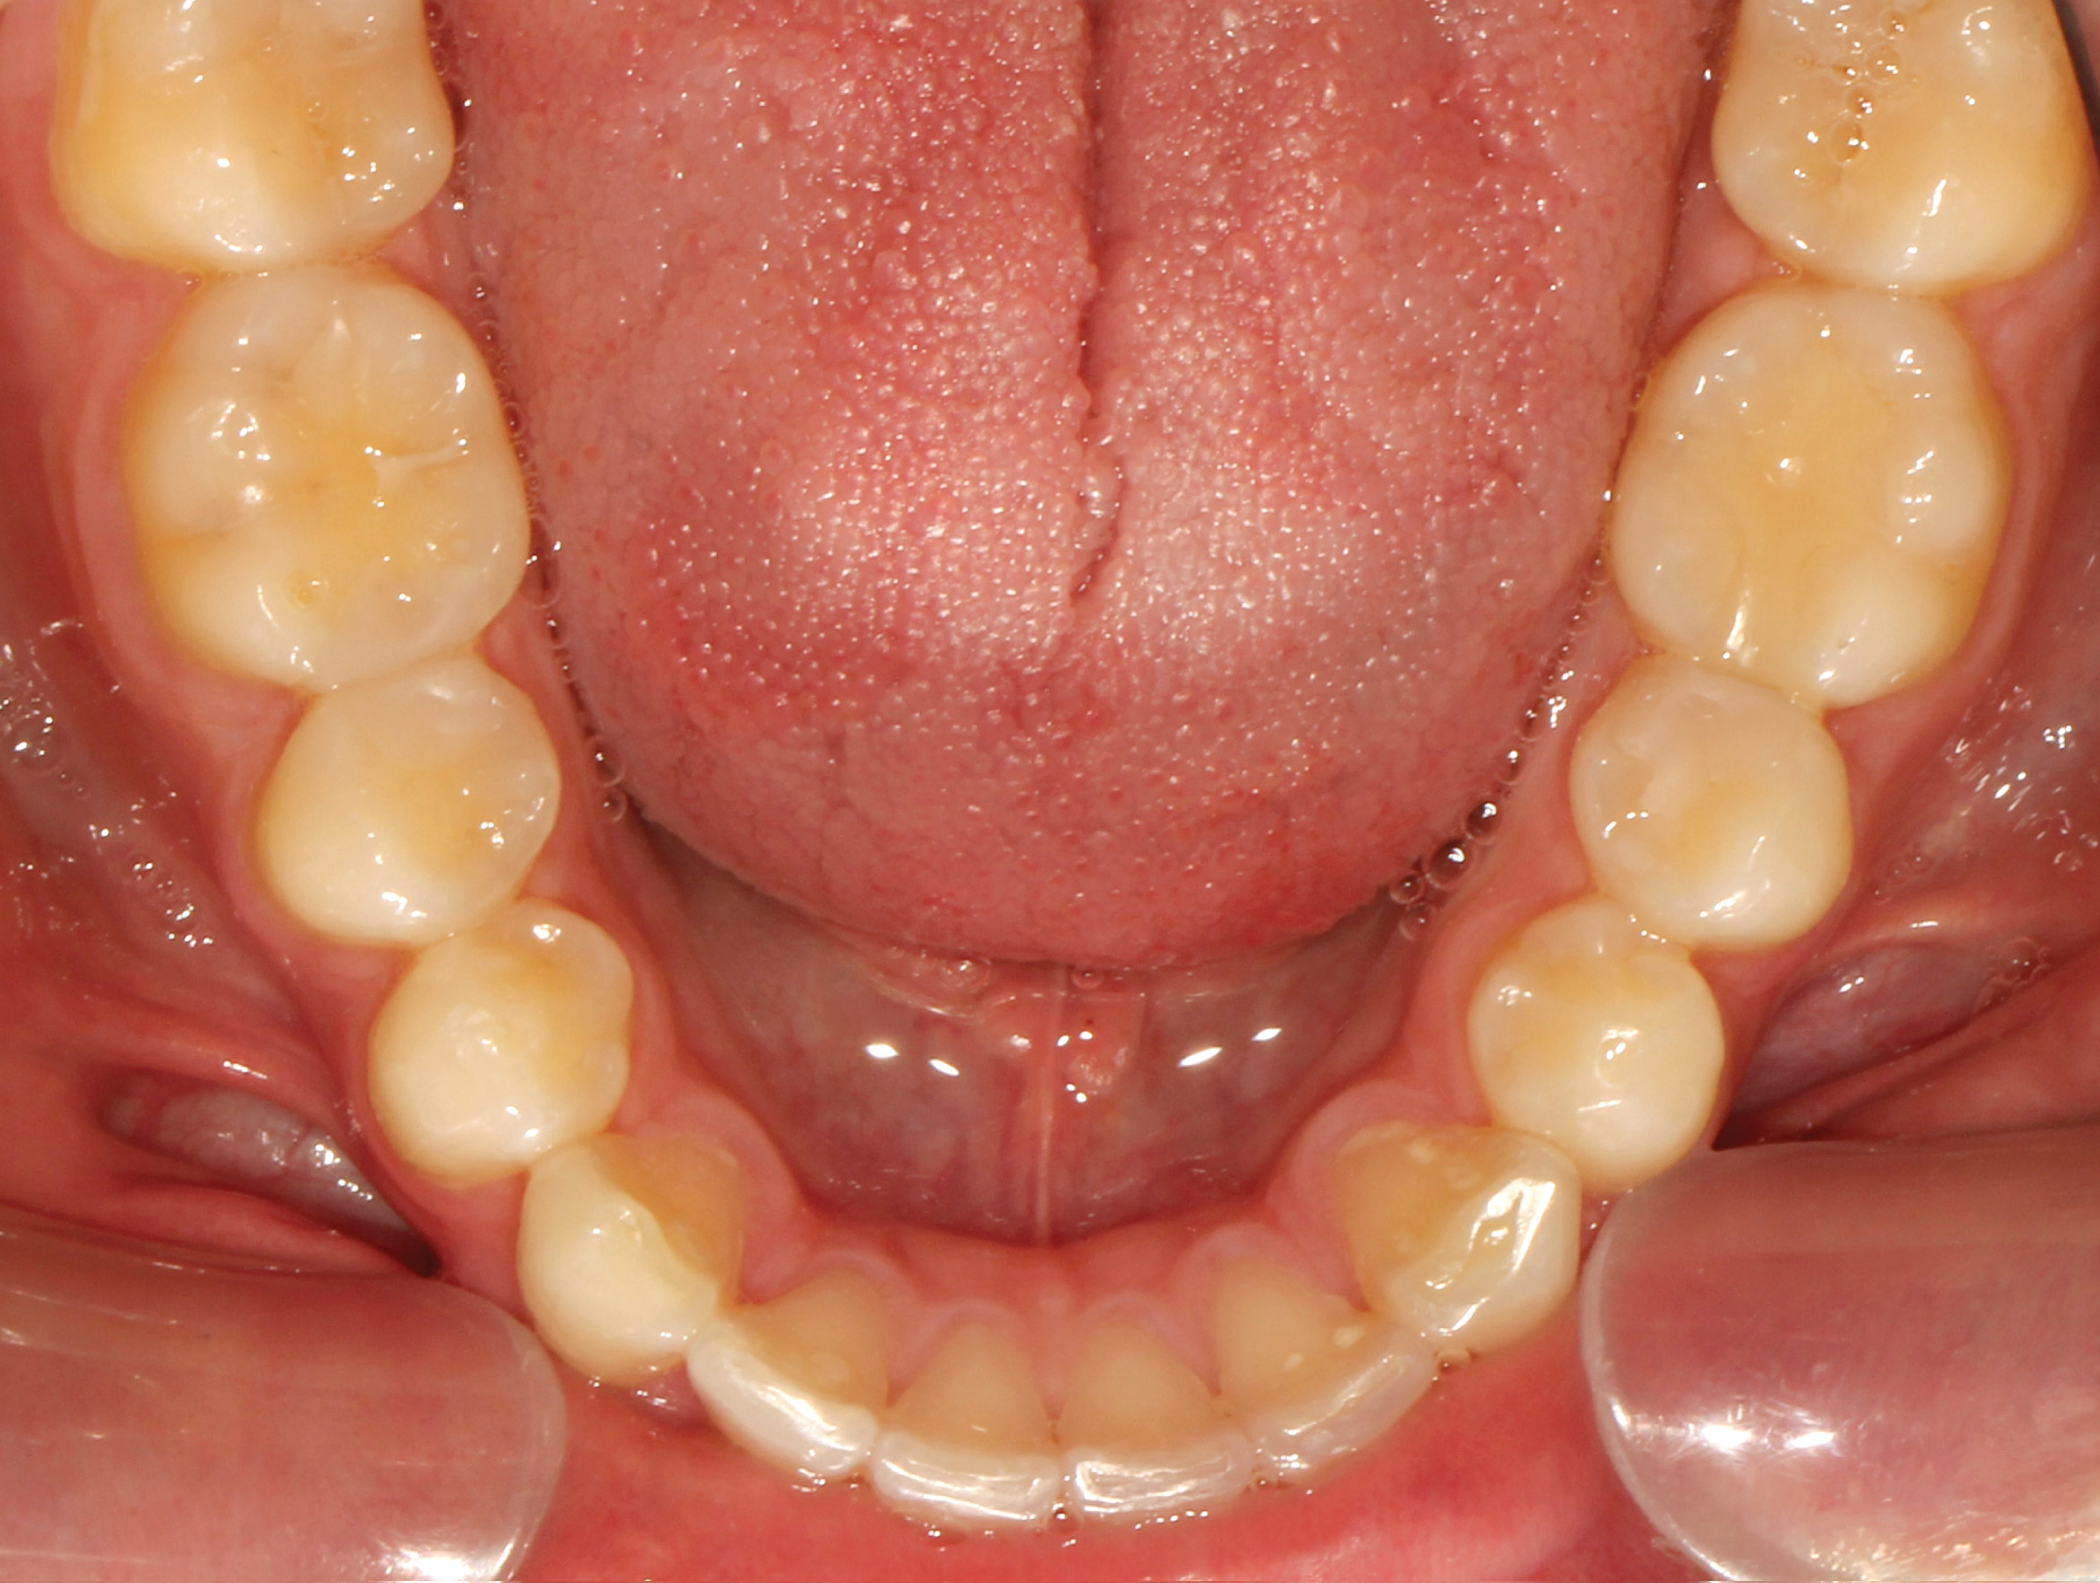

Fig. 5: Pre-op (upper occlusal view) Fig. 6: Pre-op (lower occlusal view)